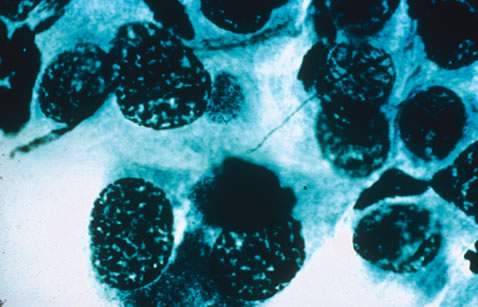

In the immunocompromised patient, other pathogens must be excluded, even in the presence of positive CMV cultures or serology. Tissue culture methods may take as long as 4 weeks. IgM antibody develops in primary infection and then disappears over 6 to 9 months, but it may reappear with reactivation of infection. The IgM test has unfortunately low specificity and sensitivity in infants and is less helpful than urine culture obtained at birth or in the first weeks of life. Any cell type may be infected, appearing larger than normal (cytomegalic) and demonstrating eosinophilic intranuclear “owl's eye” and smaller intracytoplasmic viral inclusion bodies, which are better seen with Giemsa or Papanicolaou's stains (Fig. 8). Histologic examination of tissue specimens, including bronchoalveolar lavage fluid and urine, may be useful for diagnosis.